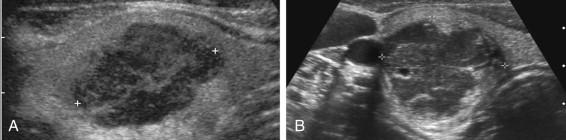

Follicular cancer accounts for approximately 10% of malignant thyroid nodules and is more common in women in the sixth decade of life. It is divided into minimally invasive (80%) and widely invasive (20%) forms. Unlike papillary cancer, follicular cancer spreads hematogenously, especially to the bone, brain, lung, and liver. Metastases to neck nodes occur in less than 5% of patients and are usually associated with locally advanced tumors. Distant metastases are present in 20% to 40% of the widely invasive variant and in 5% to 10% of the minimally invasive variant. The 20-year mortality for all patients with follicular cancer is approximately 25%. The microcalcifications and nodal metastases seen with papillary cancer are not features of follicular cancer. Follicular cancers share the same sonographic features as follicular adenomas ( Fig. 10-8 ).

F igure 10-8, Follicular cancer (cursors) in different patients. A, Transverse view shows a solid, smoothly marginated, hypoechoic nodule. B, Transverse view shows a solid, smoothly marginated nodule with a partial halo and several cystic areas.